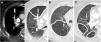

La TC torácica en espiración es una técnica complementaria de la inspiración que aporta valiosa información fisiológica y puede ser más sensible que las pruebas de función respiratoria para detectar atrapamiento aéreo. Tiene múltiples indicaciones, entre las más frecuentes están la enfermedad obstructiva de la vía aérea producida por bronquiolitis obliterante, asma, síndrome de Swyer-James, traqueomalacia, neumonitis por hipersensibilidad o sarcoidosis. En alguna de ellas, como la bronquiolitis obliterante, la TC espiratoria puede ser la única técnica de imagen que detecta alteraciones en las fases iniciales. Si queremos que sea de utilidad diagnóstica, hay que asegurarse de que el estudio tenga calidad suficiente. Para ello se recomienda explicar al paciente en qué consiste la prueba, emplear instrucciones precisas y realizar un breve entrenamiento antes de iniciar la adquisición. En este trabajo sugerimos estrategias para optimizar la técnica y proponemos un algoritmo para interpretar los hallazgos radiológicos en el contexto de la patología obstructiva pulmonar.

Expiratory CT scan is a complementary technique of inspiratory CT that provide valuable physiological information and may be more sensitive to detect air trapping than pulmonary function tests. It is useful in many obstructive airway diseases, including obliterative bronchiolitis, asthma, Swyer-James syndrome, tracheomalacia, hypersensitivity pneumonitis and sarcoidosis. In obliterative bronchiolitis, expiratory CT scan may be the only imaging technique that shows abnormalities in the early phase of disease. In order to obtain a good quality study, we should explain the procedure to the patient, use precise instructions and do some practice before image acquisition. Here we describe strategies to optimize the technique and propose an algorithm that help in interpretation of imaging findings in patients with obstructive airway disease.